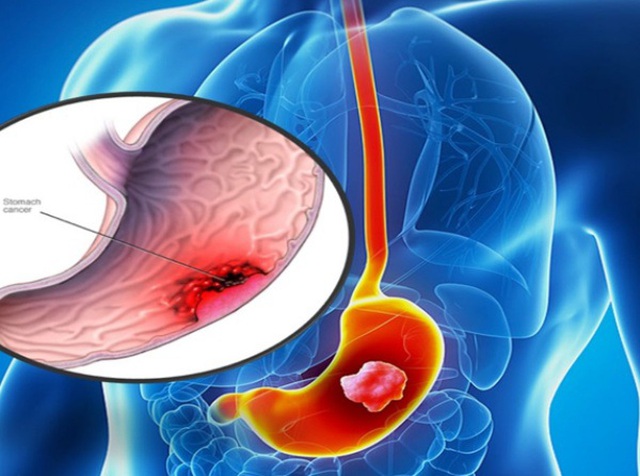

Ung thư dạ dày được xếp vào nhóm khó phát hiện sớm. Tỷ lệ bệnh nhân ở Việt Nam được chẩn đoán ở giai đoạn đầu rất hiếm. Ước tính mỗi năm nước ta có khoảng 10.400 người bệnh được phát hiện.

Theo dự báo số ca ung thư dạ dày được phát hiện tại nước ta sẽ tăng lên khoảng 11.500 ca vào năm 2020. Tại Bệnh viện K, một năm chỉ có khoảng 30 ca được chẩn đoán ở giai đoạn sớm trong số hàng nghìn bệnh nhân. Vì thế, tỷ lệ bệnh nhân sống sau 5 năm chưa cao.

Ung thư dạ dày thường được phát hiện muộn.

Việc chữa trị cho bệnh nhân ung thư, đặc biệt là những trường hợp phát hiện bệnh ở giai đoạn cuối còn nhiều hạn chế. Đến nay các nhà khoa học vẫn chưa khẳng định được nguyên nhân trực tiếp của thư dạ dày. Vì thế, đề phòng bệnh là đề phòng các yếu tố nguy cơ.